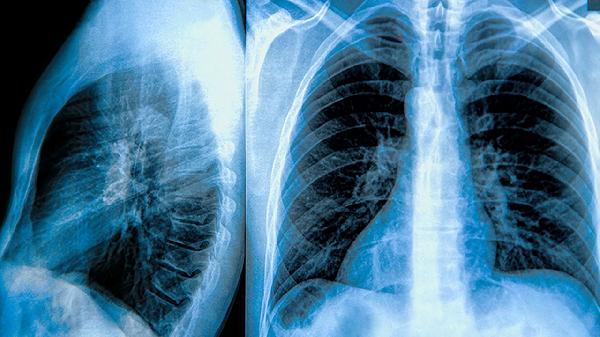

1、肺大泡是肺泡壁破裂后形成的囊状结构,常见于慢性阻塞性肺疾病COPD患者。未治疗的肺大泡会逐渐增大,压迫周围正常肺组织,导致肺功能下降,患者可能出现持续性呼吸困难,尤其在活动后加重。长期缺氧还可能影响心脏功能,增加肺心病的风险。

3、肺大泡破裂是另一个严重的风险,破裂后空气会进入胸膜腔,形成气胸。气胸会导致突发性胸痛和呼吸困难,严重时可能危及生命,需要紧急处理。气胸还可能反复发作,进一步影响患者的生活质量。